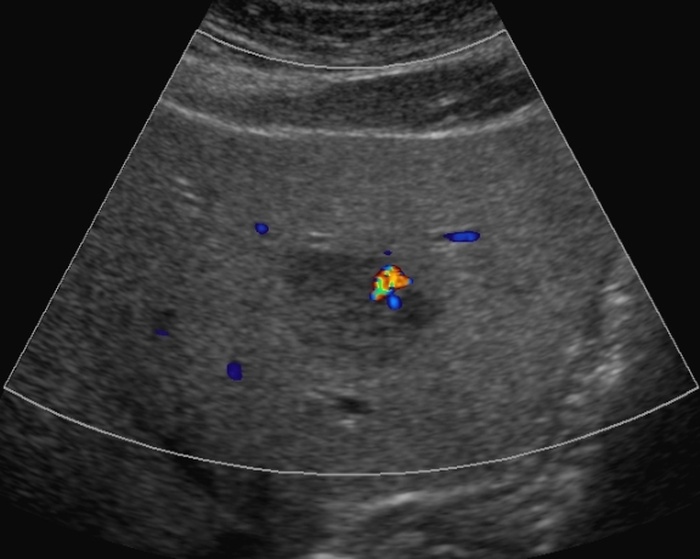

Hepatofugal flow